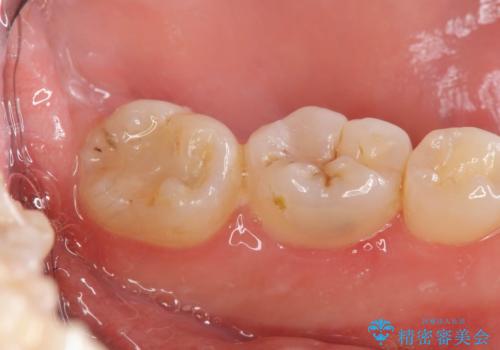

- 親知らずの抜歯を希望され来院されましたが手前の大臼歯2本に虫歯が認められ、治療が必要な状態でした。

クラウン形態にするには歯の高さが足りず設計できないため、親知らずの抜歯と共に歯周外科を同時に行うことで安定した歯周組織を獲得しセラミック治療を行う治療計画としました。

歯冠長の延長を行ったことで、安定したクラウン治療を行うことができました。